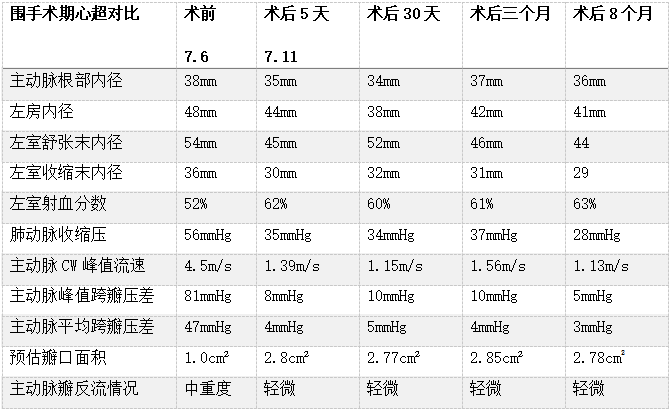

2022年7月6日,葛均波院士及其团队的周达新主任医师、潘文志主任医师、郭克芳副主任医师以及张晓春、张源、陈莎莎、李伟等医师,成功完成世界首例聚合物瓣膜(SIKELIA™)经导管主动脉瓣置换术。该例为80岁男性患者,主要症状为反复活动后胸闷气促,诊断重度主动脉瓣狭窄、心房颤动、高血压。TAVR术程顺利,导管操作时间(skin to skin)27分钟,器械操作顺畅。术后造影显示,瓣膜工作状态良好,跨瓣压差正常,瓣周漏微量。冠脉无阻塞,无传导阻滞。术后即刻拔除气管插管,顺利苏醒。术后六天复查心超提示人工瓣架固定,开放不受限,峰值压差8mmHg,平均压差4mmHg,轻微主动脉瓣反流。患者恢复良好,氨基末端利钠肽前体由术前5688pg/ml下降至1035pg/ml,NYHA 心功能分级由III级改善至II级。术后30天、3个月、8个月随访发现主动脉瓣无明显跨瓣压差,仅微量反流。

术后随访

8个月随访情况